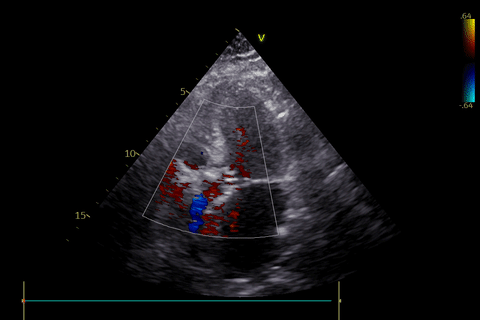

患者一超声报告:

超声报告:

术前超声评估:

患者二术后超声评估

患者三术后超声评估